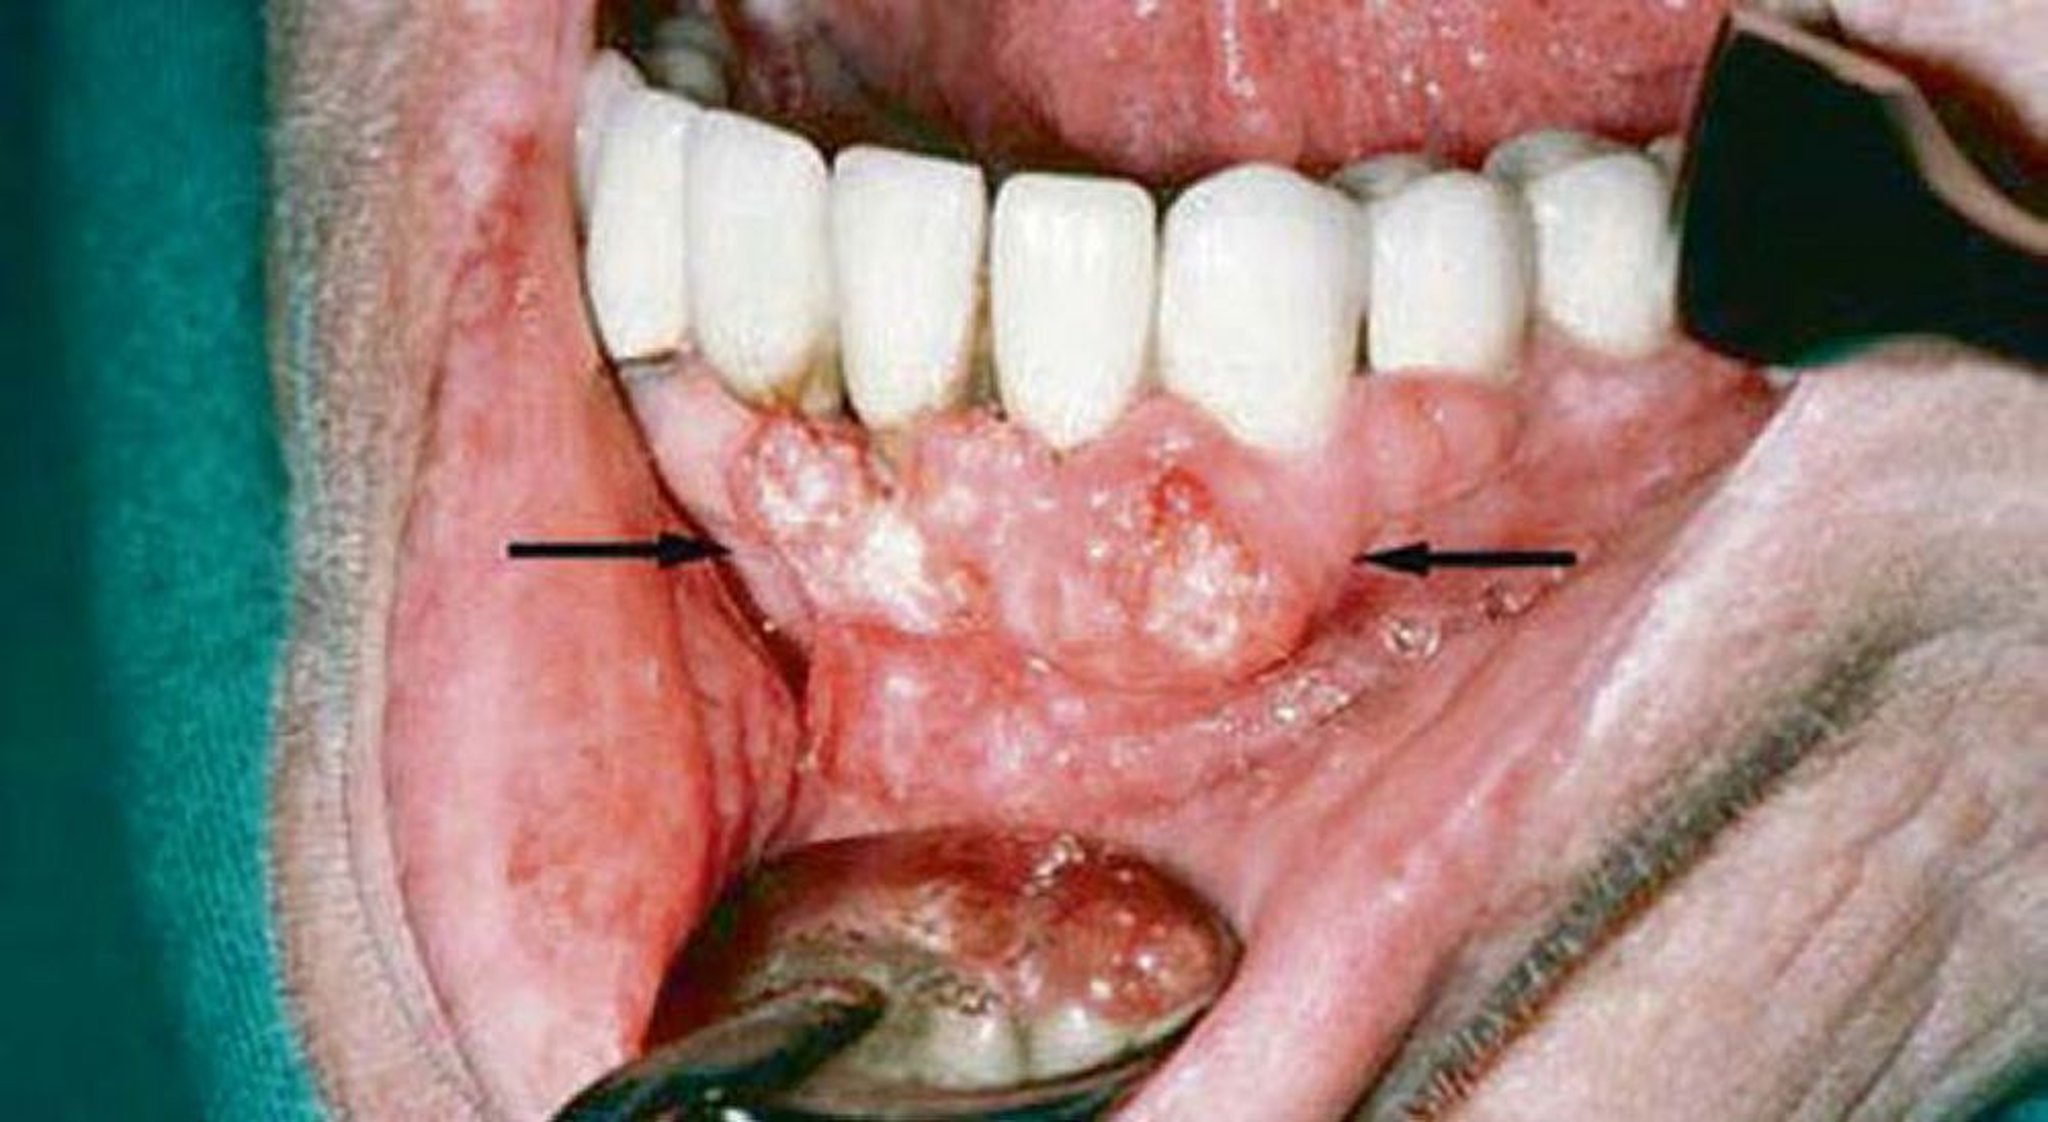

Carcinome malpighien (lésions gingivales)

L'examen gingival de ce patient a mis en évidence un carcinome malpighien. L'imagerie a montré une invasion de la mandibule.